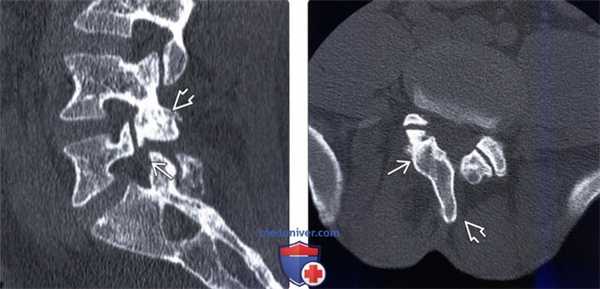

(Слева) КТ, сагиттальный-срез: у пациента с врожденным незаращением межсуставной части дуги определяется ограниченный хорошо выраженными кортикальными краями широкий дефект МЧ дуги L5 в сочетании с гипертрофией и дисморфизмом нижнего суставного отростка L4.

(Справа) КТ, фронтальный срез: у пациента с врожденным незаращением правой межсуставной части дуги отмечается увеличение размеров и гипертрофия правой пластинки дуги и ротация остистого отростка.